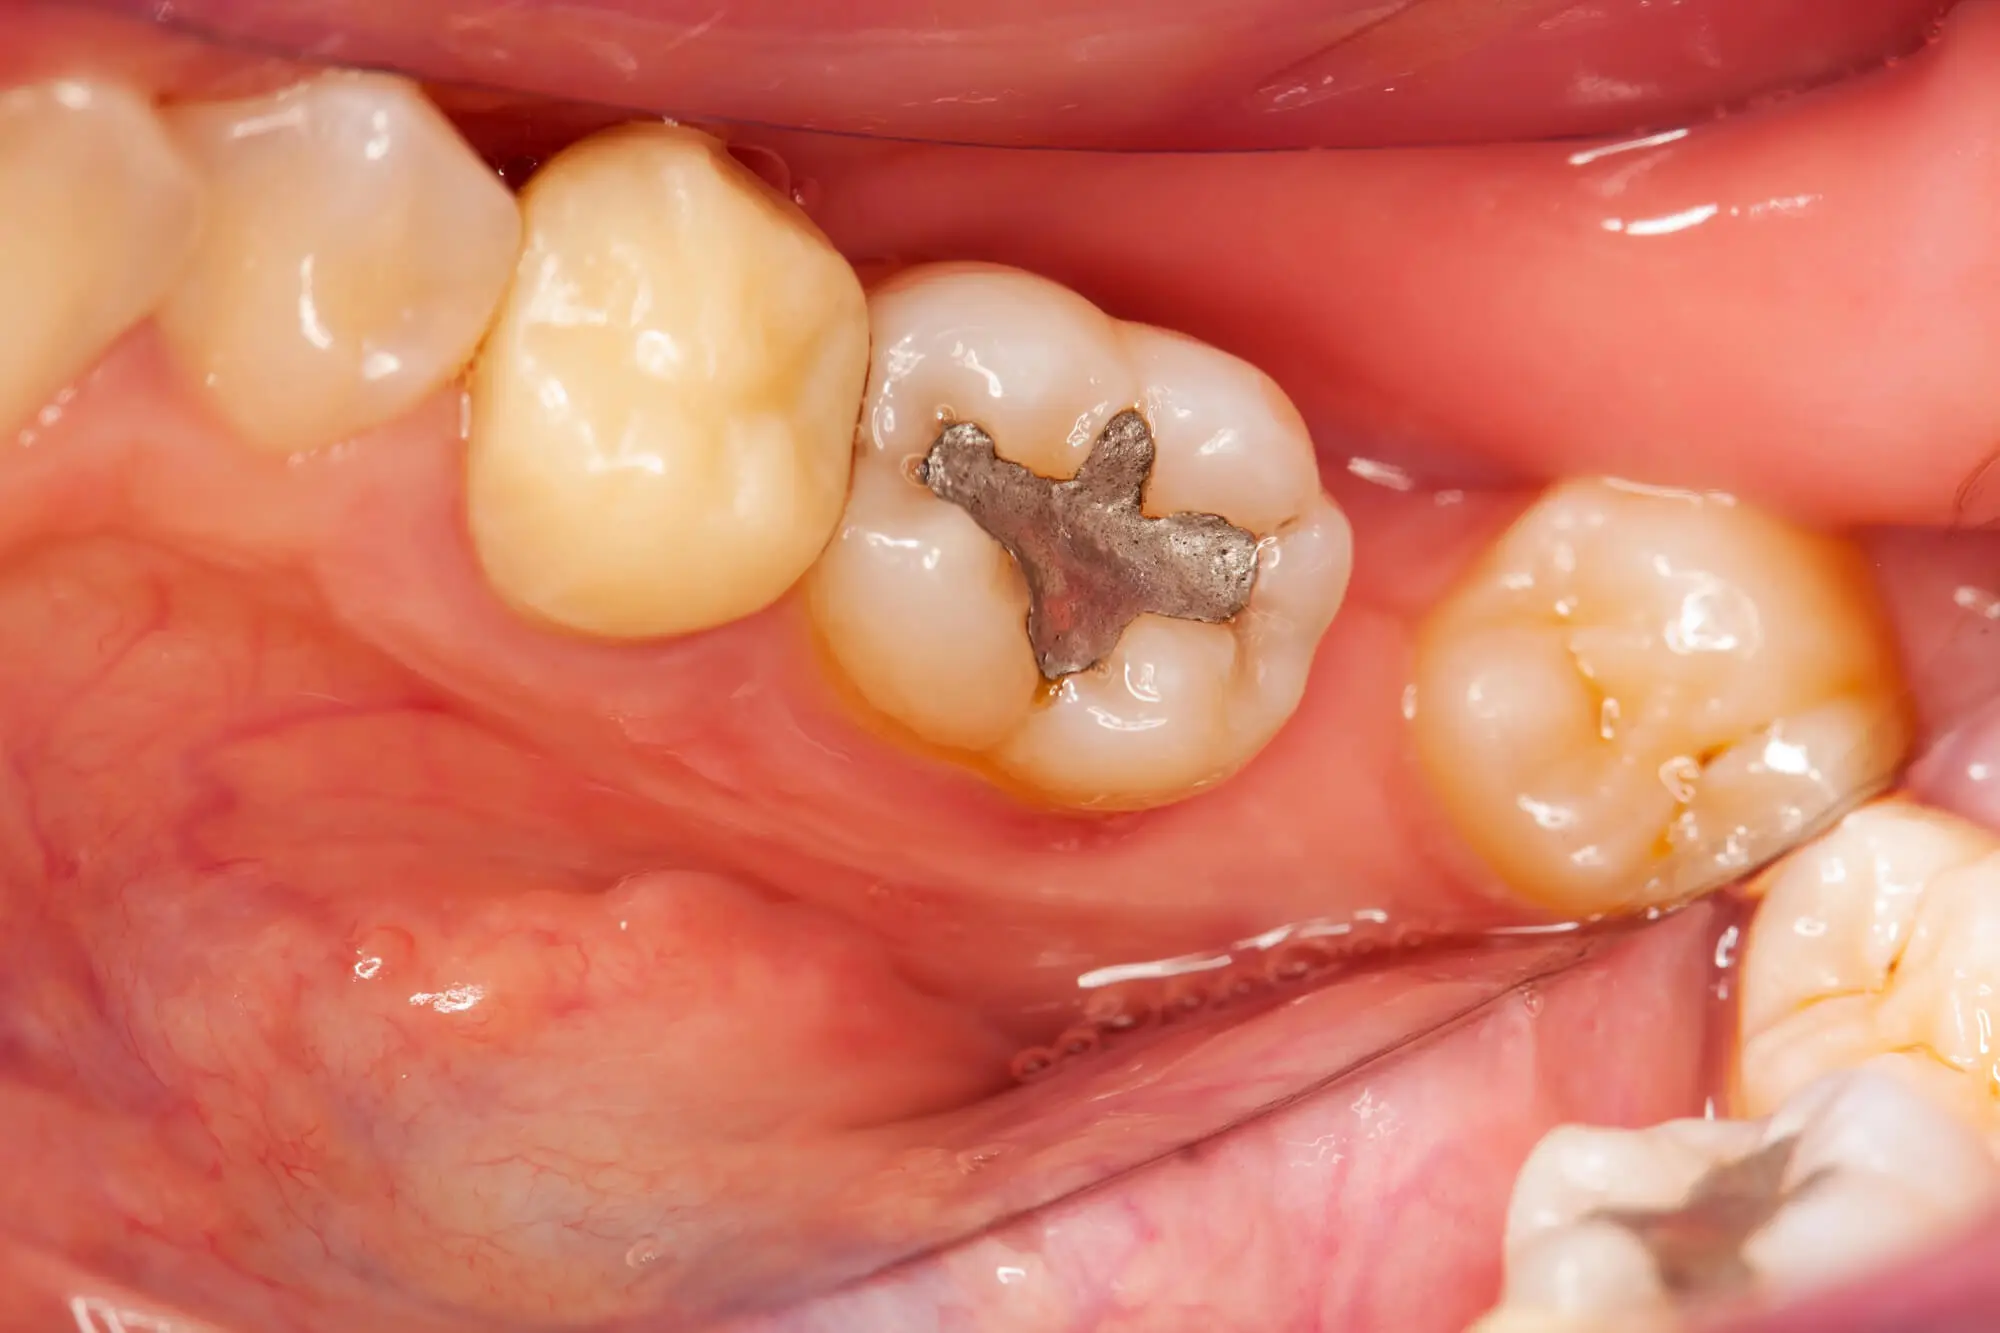

What Are Amalgam Fillings?

Amalgam fillings are durable, silver-colored dental materials made from a mixture of metals. They’re commonly used for back teeth due to the belief that these metal restorations are more long-lasting and resistant to wear.

Moreover, their lack of aesthetic appeal can be counteracted as these teeth aren’t easily visible.

- Mercury (50%): Due to its stability, moldability, and capacity to fuse other metals, mercury is the main ingredient in amalgam fillings. Although mercury is toxic in its pure form, it is considered safe in dental amalgam fillings because it hardens when combined with other powdered metals.

- Silver (22–32%): Silver is added to increase the amalgam mixture’s strength and durability. It improves the material’s resistance to corrosion and lends the filling its distinctive silver-gray hue.

- Tin (14–30%): Tin makes the amalgam more workable and malleable, facilitating the filling’s placement in the cavity. When exposed to temperature changes in the mouth, it also helps the alloy expand and contract without breaking.

- Copper (6–14%): Copper is added to improve the amalgam’s strength and resistance to wear. It also lessens the possibility of corrosion, extending the filling’s lifespan.

- Other Elements: Trace amounts of palladium, zinc, or other metals may be added to improve the material’s qualities even further.